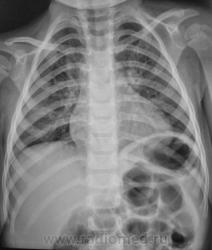

Пол пациента: Женский пол Тип патологии: Воспалительное заболевание неинфекционной природы Область исследования: Грудная клетка и верхние дыхательные пути Методы исследования: Rg Пациентка из детского отделения направлена на рентгенографию органов грудной полости с диагнозом - "Пневмония". Ваше мнение уважаемые коллеги? https://radiomed.ru/sites/default/files/styles/case_slider_image/public/user/12/2.Rebyonok.jpg?itok=dMaaWYGH ID:1367 Сб, 20/02/2010 - 22:53 #1 Анатолий Владим... Не на сайте Был на сайте: 7 лет 11 месяцев назад Зарегистрирован: 16.10.2009 - 21:16 Публикации: 1941 Пневмонической инфильтрации не видно. Вс, 21/02/2010 - 16:48 #2 Vikkur Не на сайте Был на сайте: 4 года 8 месяцев назад Зарегистрирован: 24.09.2009 - 14:34 Публикации: 1749 Не могу исглючить бронхообструктивного синдрома. Виктор. Втр, 23/02/2010 - 09:59 #3 Николай Не на сайте Был на сайте: 2 года 10 месяцев назад Зарегистрирован: 29.05.2009 - 04:38 Публикации: 554 Рентгенологических признаков пневмонии нет, легочная ткань без изменений. О бронхобструкции также речи нет. Пнд, 28/03/2011 - 08:02 #4 гана Не на сайте Был на сайте: 4 года 1 месяц назад Зарегистрирован: 12.01.2011 - 09:43 Публикации: 84 какая то рахитеческая грудная клетка,да и рисунок легочной выражен в прикорневой зоне больше слева, а сердечко - не увеличены левые границы? УЗИ сердца делали? - может врожденная патология?петли кишечника пневматизированы.

Пневмонической инфильтрации не видно.

Не могу исглючить бронхообструктивного синдрома.

Рентгенологических признаков пневмонии нет, легочная ткань без изменений. О бронхобструкции также речи нет.

какая то рахитеческая грудная клетка,да и рисунок легочной выражен в прикорневой зоне больше слева, а сердечко - не увеличены левые границы? УЗИ сердца делали? - может врожденная патология?петли кишечника пневматизированы.